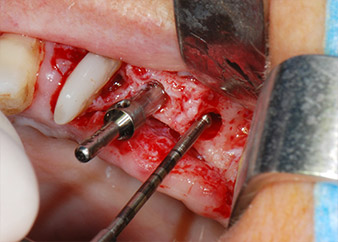

Implant beds were prepared at sites 25 and 26 with rotary instruments, used in a contra-angle handpiece with a 20 : 1 transmission ratio with an updated powerful implant motor (Implantmed, W&H) (Fig. 8).

The implants (Restore, Keystone Dental, diameter 3,75 mm, length 8.0 mm) were placed with the implant motor

(Figs. 11 and 12).